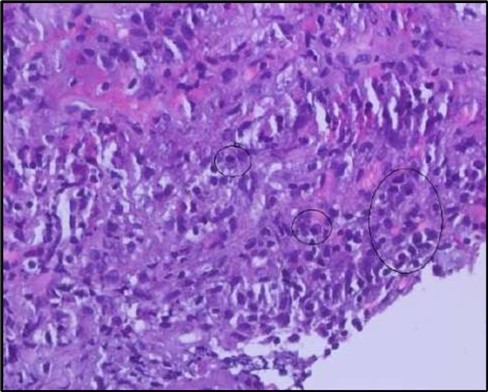

Two weeks post-surgery, the left eye showed significant healing, with a small conjunctival granuloma and vascularization at the ulcer margins. The cornea was clear with a central leading edge nasally, deep and quiet anterior chamber and clear lens. VA 6/6 bilaterally and IOP normal. Histopathology of excised conjunctiva showed non-keratinized squamous epithelium with superficial erosions, stromal elastosis, hemorrhage, and inflammatory infiltration, but no signs of granulomatous disease, malignancy, or viral evidence, findings consistent with idiopathic localized inflammatory process. The patient reported significant relief and satisfaction post-surgery, resuming normal activities. Treatment continued with oral prednisolone 25 milligrams every other day, tobramycin-dexamethasone ointment twice daily, and preservative-free artificial tears four times daily Figure 4, Figure 5a, Figure 5b, Figure 5c, Figure 5d.

Figure 5b.OS, High-power H&E view showing dense inflammatory infiltration within the corneal stroma composed predominantly of lymphocytes and numerous plasma cells (circles highlight plasma cells).

Histopathological examination revealed a dense infiltration of CD138-positive plasma cells within the excised conjunctival tissue (Figure 5b, Figure 5c, Figure 5d). This finding supports an antibody-mediated immunopathogenesis in Mooren’s ulcer, consistent with Type II and Type III hypersensitivity mechanisms described in the literature 20, 21. The prominent presence of CD138- positive plasma cells provide a clear pathological rationale for conjunctival resection, as excision of the immunologically active perilimbal conjunctiva effectively removes the local 'factory' of autoantibodies that drive corneal stromal destruction, thereby halting ongoing tissue damage 21.